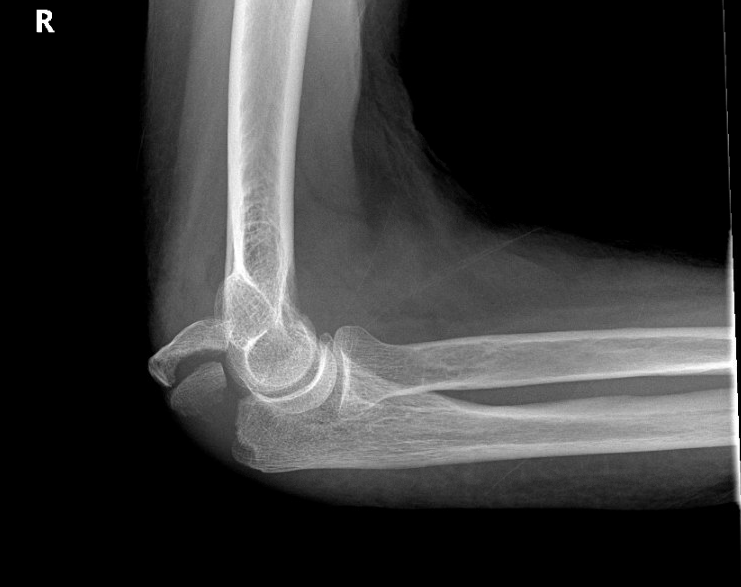

This a “displaced” fracture of the olecranon at the elbow.

Often, the simplest description and way to assess fractures is “non-displaced” vs “displaced”.  Non displaced means there is a fracture through a bone, but the alignment is normal.  I.e., all the pieces of the bone remain in place.  With few exceptions, non displaced fractures generally heal without complications and sometimes require very minimal treatment.  Oftentimes, non displaced fractures are supporting with a brace or wrap, and patients can use pain as a guide to return to activity and use.